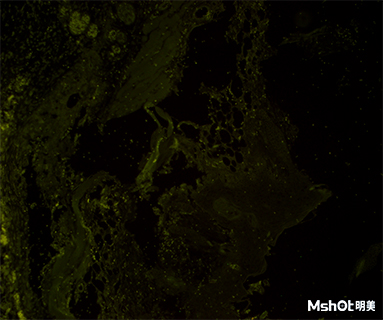

香港大學(xué)深圳醫(yī)院骨科研究實(shí)驗(yàn)室老師已有奧林巴斯倒置顯微鏡,需要看熒光組織切片,要求熒光成像清晰,現(xiàn)需要通過三目鏡筒連接顯微鏡相機(jī)與圖像系統(tǒng),實(shí)現(xiàn)對鏡下成像的保存、分析等

為廣大顯微成像用戶提供實(shí)時(shí)全方位貼心服務(wù),明美公司在全國十多處設(shè)有辦事處,深圳工程師和老師溝通確認(rèn)具體需求后推薦明美顯微鏡相機(jī)MC50-S,這款顯微鏡相機(jī)采用全局快門芯片、USB3.0數(shù)據(jù)傳輸接口,具有較高的清晰度和靈敏度、色彩還原真實(shí)、傳輸數(shù)據(jù)快的優(yōu)點(diǎn)。極其適合在弱光環(huán)境下或顯微技術(shù)領(lǐng)域中使用,在對色彩要求高的領(lǐng)域表現(xiàn)同樣優(yōu)異,如:熒光成像、病理分析等。